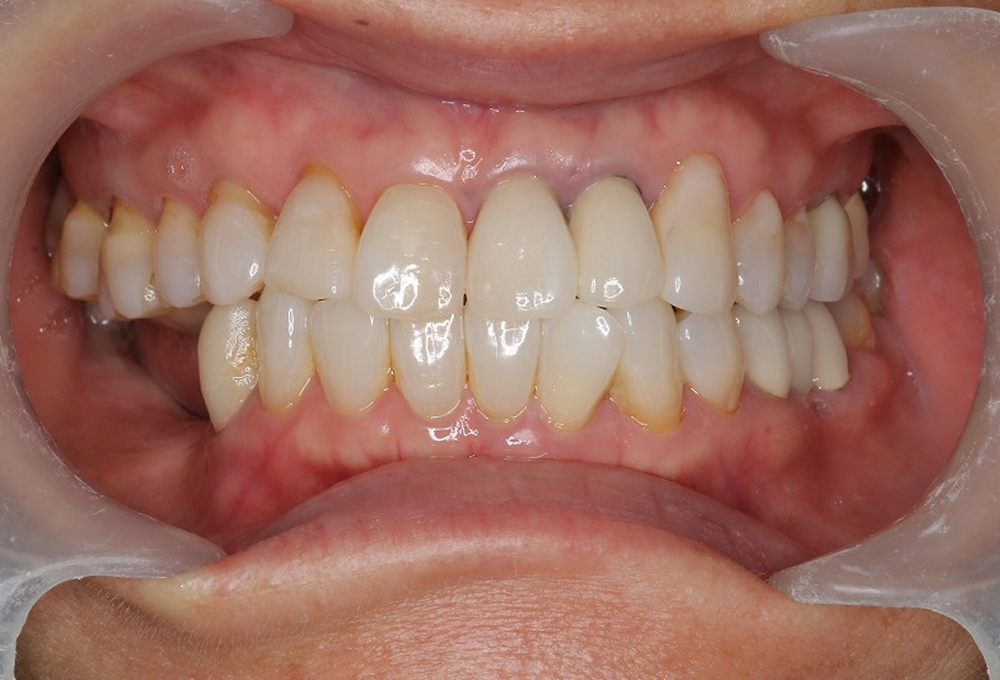

⑥術後 ホワイトニング後セラミックにて修復